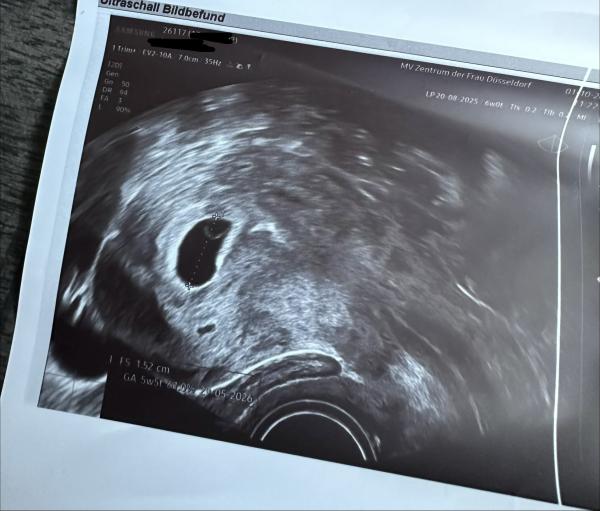

ich hoffe, es geht euch gut! Ich bin ganz neu hier umd momentan in der aufregenden Phase meiner Schwangerschaft. Ich habe heute mein erstes Ultraschallbild erhalten. Ich bin bei 6+0 und es wurde ein winziges Embryo sichtbar, aber leider konnte man den Herzschlag noch nicht wirklich erkennen. Mein Frauenarzt sagt es sei aber gut entwickelt und es schaut alles super aus. Er hat mir nun für nächste Woche einen weiteren Termin gegeben.